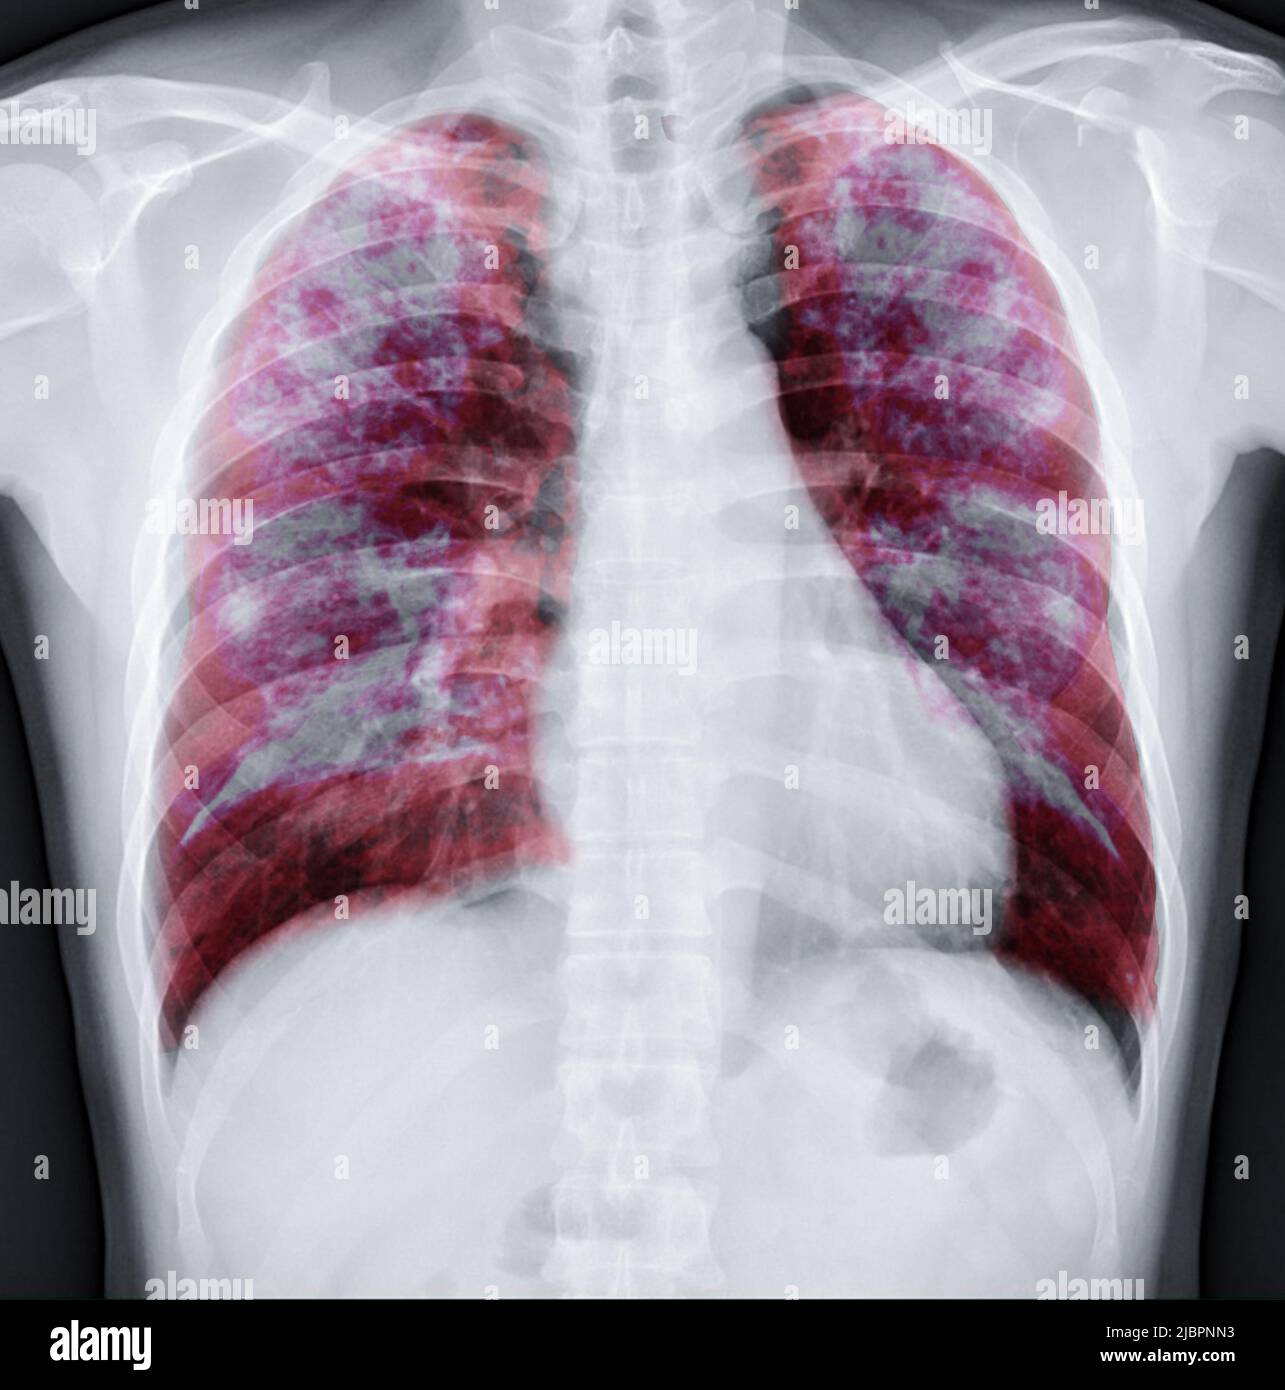

Fusion des rayons X du thorax avec l'image de rendu Lung 3D pour le diagnostic TB, TB et Covid-19 de CT-scanner 3D.